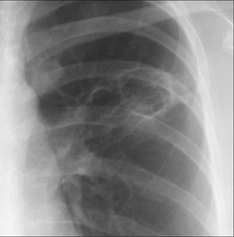

image

Figure 30.8 Haemoptysis in a young patient with cystic fibrosis. The CXR shows extensive bronchiectasis: ring shadows (cystic dilatation of bronchi) and tramline shadows (bronchial wall thickening). The chronic inflammation erodes friable mucosal vessels and causes bleeding.